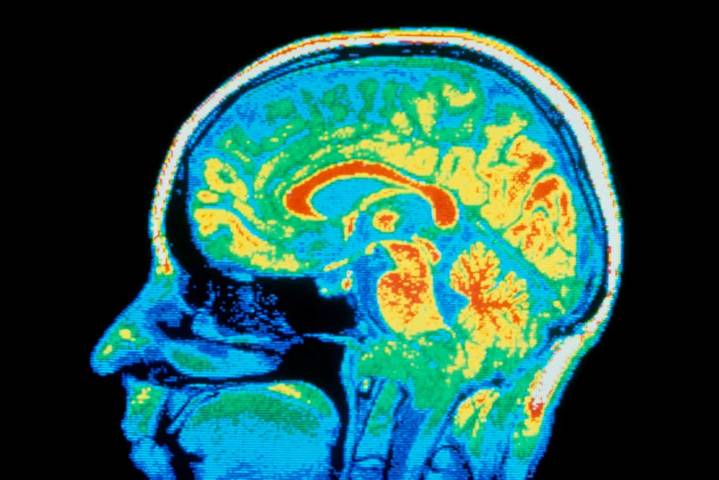

People are often diagnosed with multiple neurodivergencies and mental health conditions, but the biggest genetic analysis so far suggests many have shared biological causes

Supposedly distinct psychiatric conditions may have same root causes